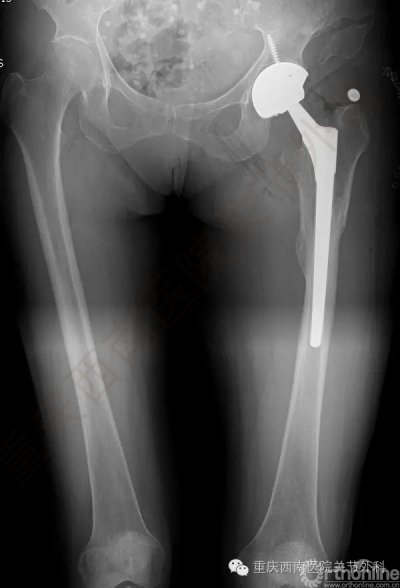

5月17日上午9:30,杨柳教授为赵女士实施了个体化导航器辅助下的全髋关节置换术。(图6)

手术耗时1小时50分钟,术中失血量100ml。术后第二天患者下地部分负重行走训练,5天患者康复出院。术后X片如图。